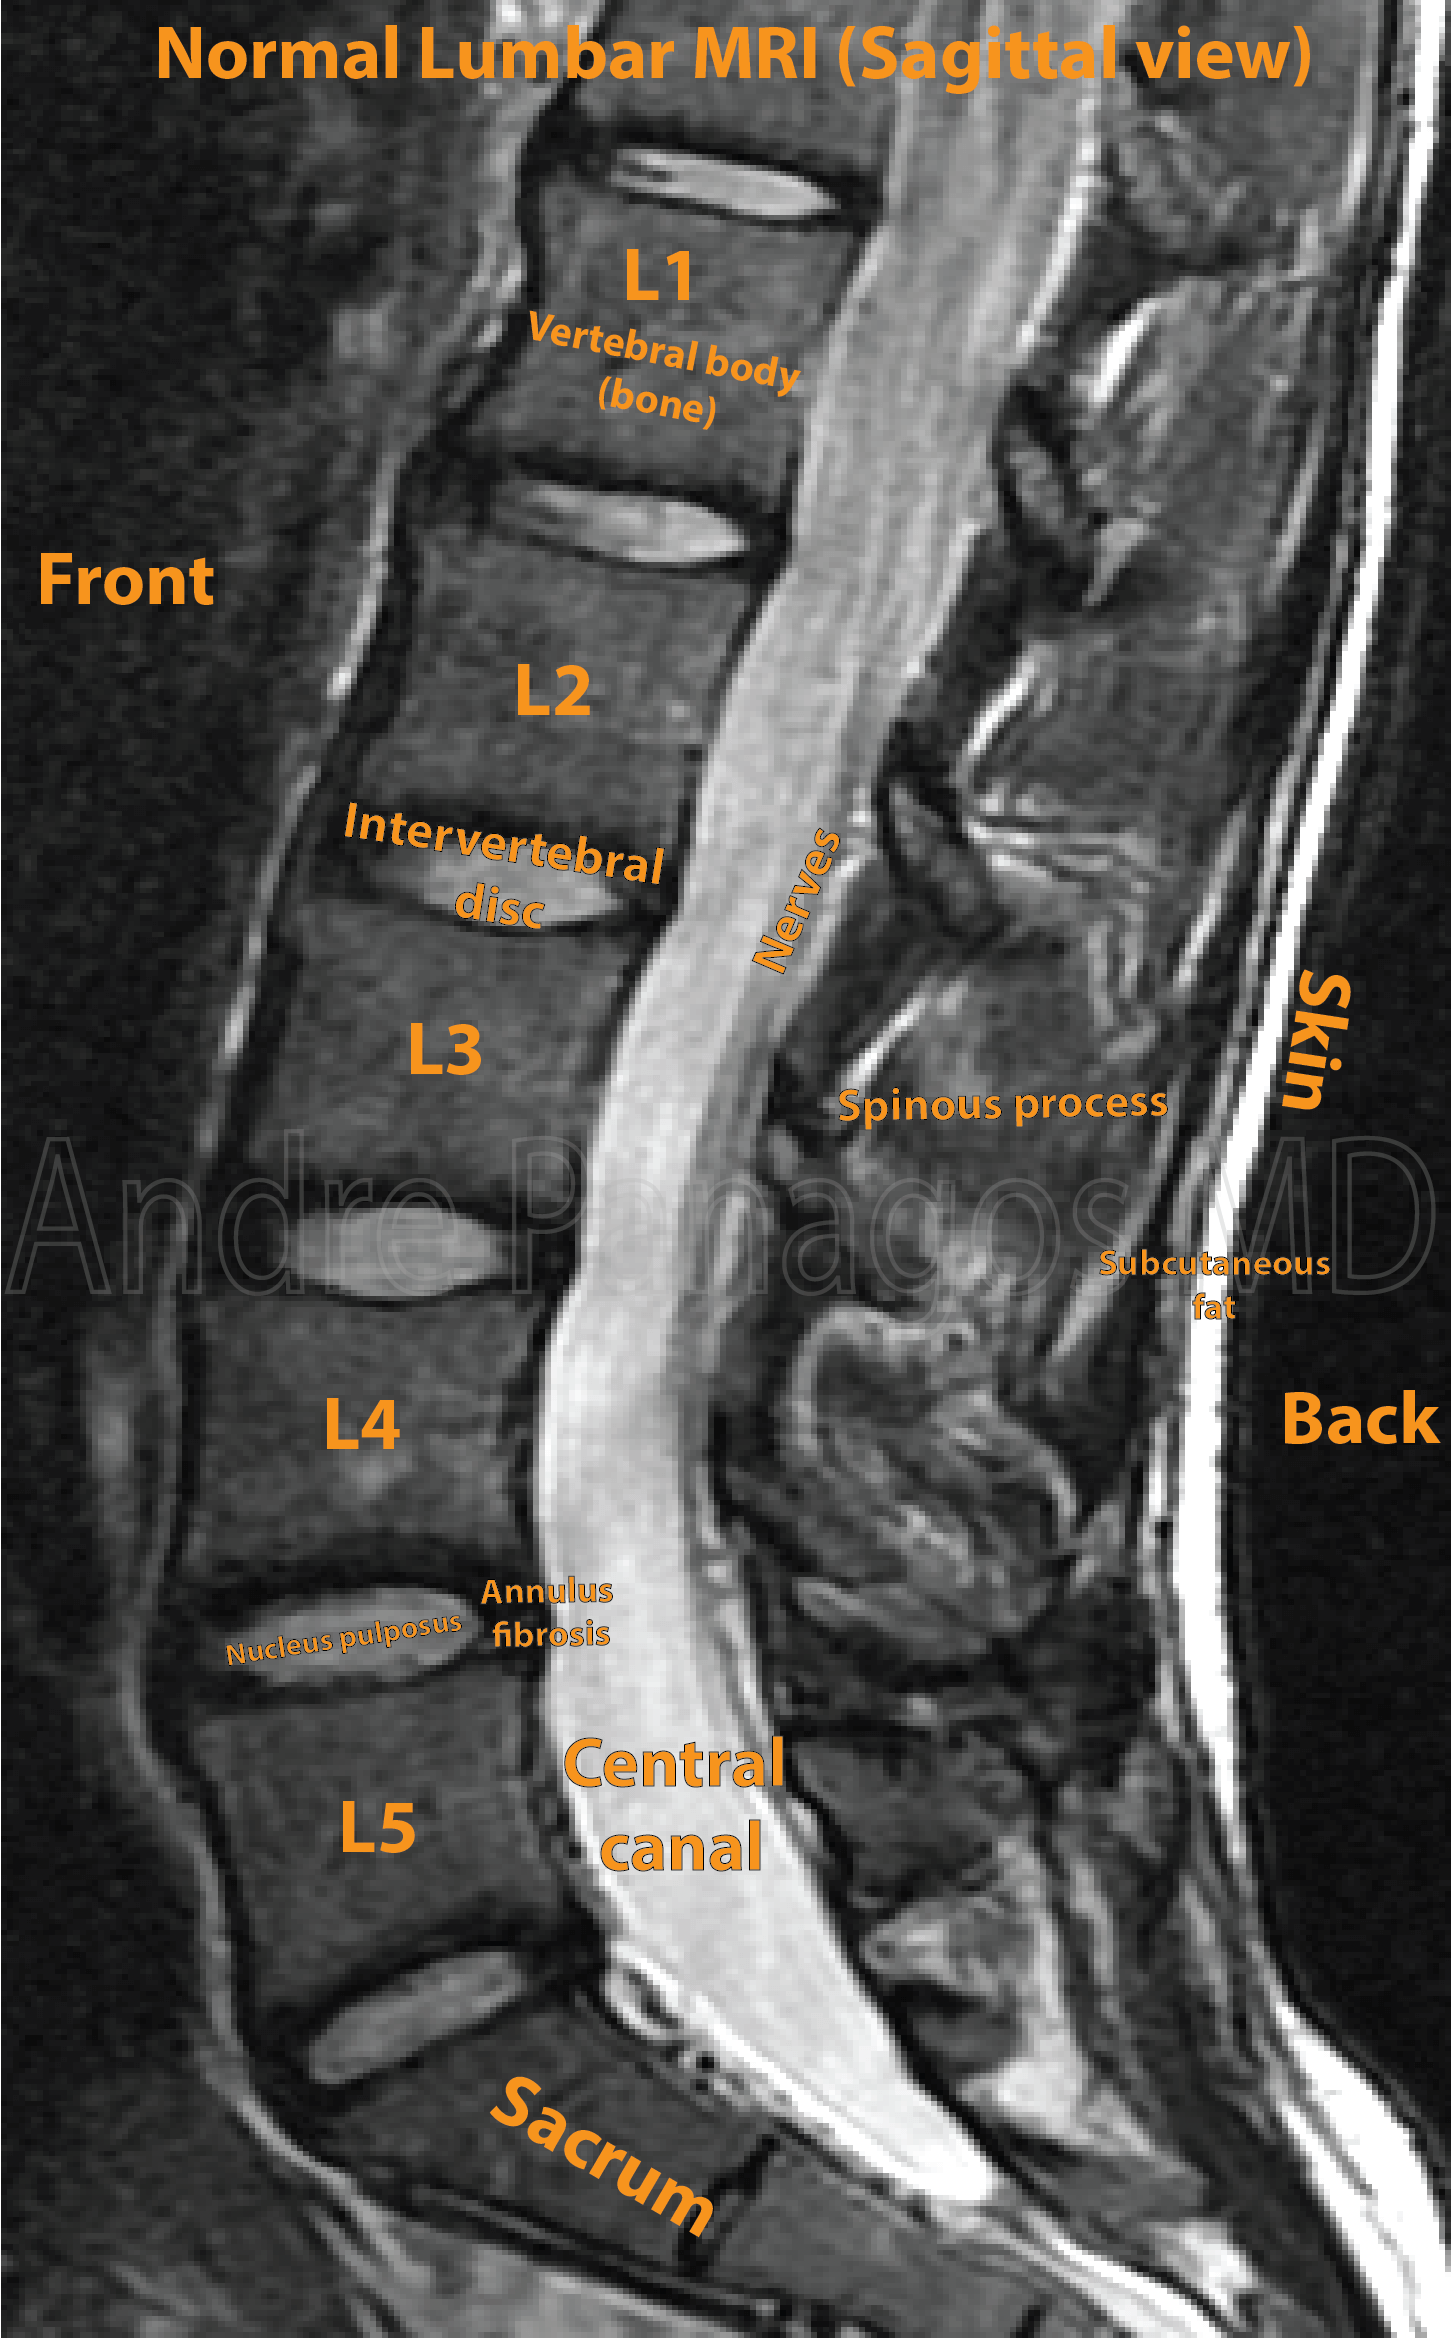

Understand what a normal lumbar MRI looks like. Our expert guide breaks down spinal anatomy, disc health, and nerve root integrity shown in diagnostic imaging. Learn how radiologists interpret clear results, identifying essential markers of a healthy lower back while distinguishing common findings from potential abnormalities to help you better understand your spine health and diagnostic reports.

Read full article: Normal Lumbar Mri